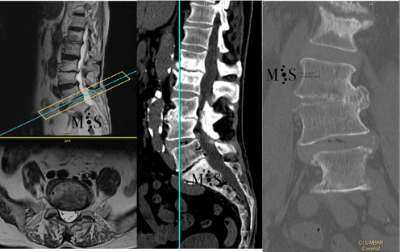

Escoliosi degenerativa

L'escoliosi és la deformitat de la columna vertebral en el pla frontal. La escoliosis pot ser congènita (des del naixement) o degenerativa (es pot adquirir amb l’edat). La degeneració progressiva dels discs intervertebrals (per l’edat, el pes i l’activitat) pot comportar que la columna es deformi amb els temps i acabi generant-se una escoliosi degenerativa o "de novo" (perquè ha aparegut de forma "nova", al contrari que en l’escoliosi congènita que sempre a estat allà des del naixement).

Les escoliosis provoquen una deformitat progressiva de l’esquena i el pacient no pot caminar recte. A més, les escoliosis poden provocar dolor lumbar i a tota l’esquena. També és possible que per la deformitat hagi arrels nervioses pinçades pels discos degenerats, resultant en un dolor irradiat per una o dues cames.

En aquests casos la cirurgia està indicada per corregir la deformitat i sobre tot per alleujar el dolor causat per l’escoliosi degenerativa. En els casos més severs d’escoliosi fins i tot pot ser necessari realitzar una osteotomía (tallar parcialment una vèrtebra) per poder redreçar la columna vertebral deformada del pacient.